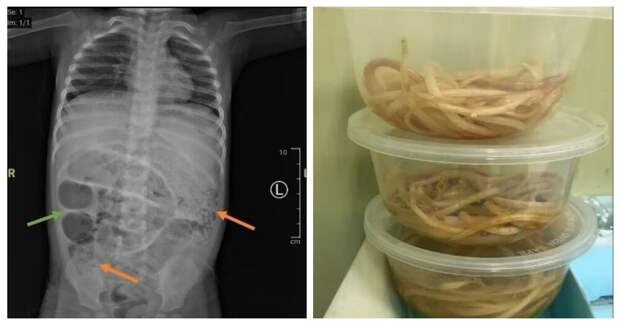

В Индонезии врачи обнаружили десятки извивающихся червей в кишечнике трёхлетнего мальчика. У ребёнка вздулся живот и поднялась температура, он не мог сходить в туалет в течение трёх дней, прежде чем его родители обратились за медицинской помощью.